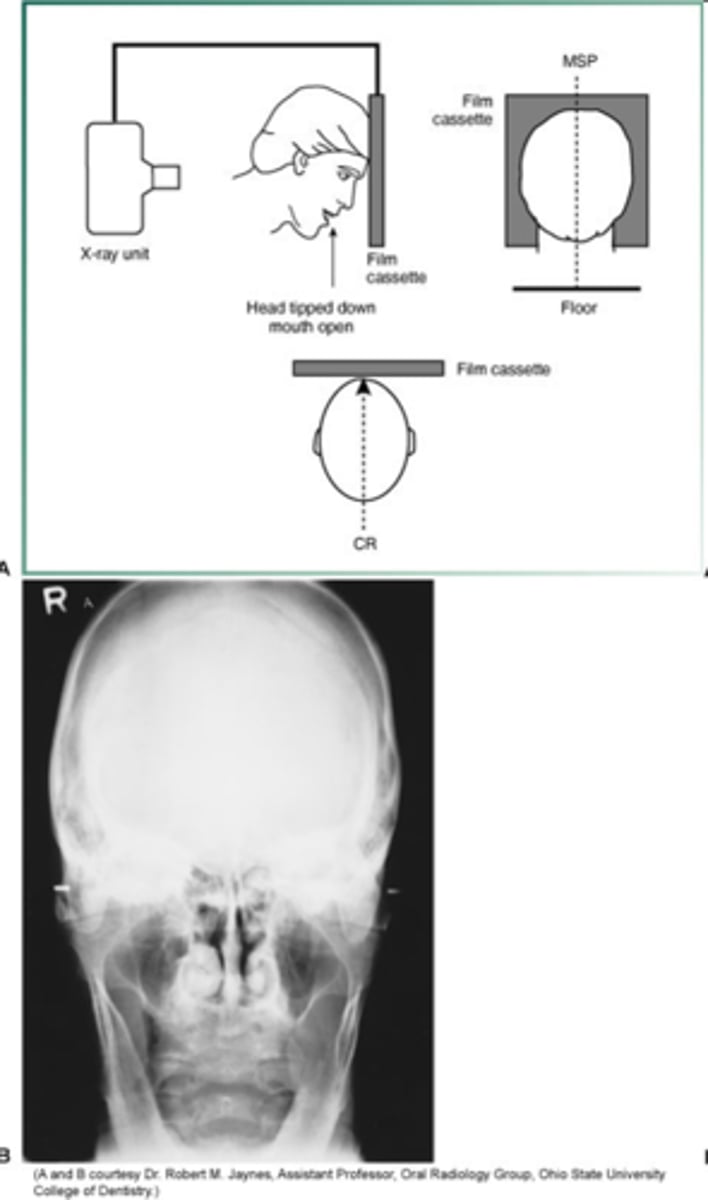

reverse town projections

identify fractures of the condylar neck and ramus

reverse towne projection head position

- head tipped down

- mouth open

- top of forehead touches receptor